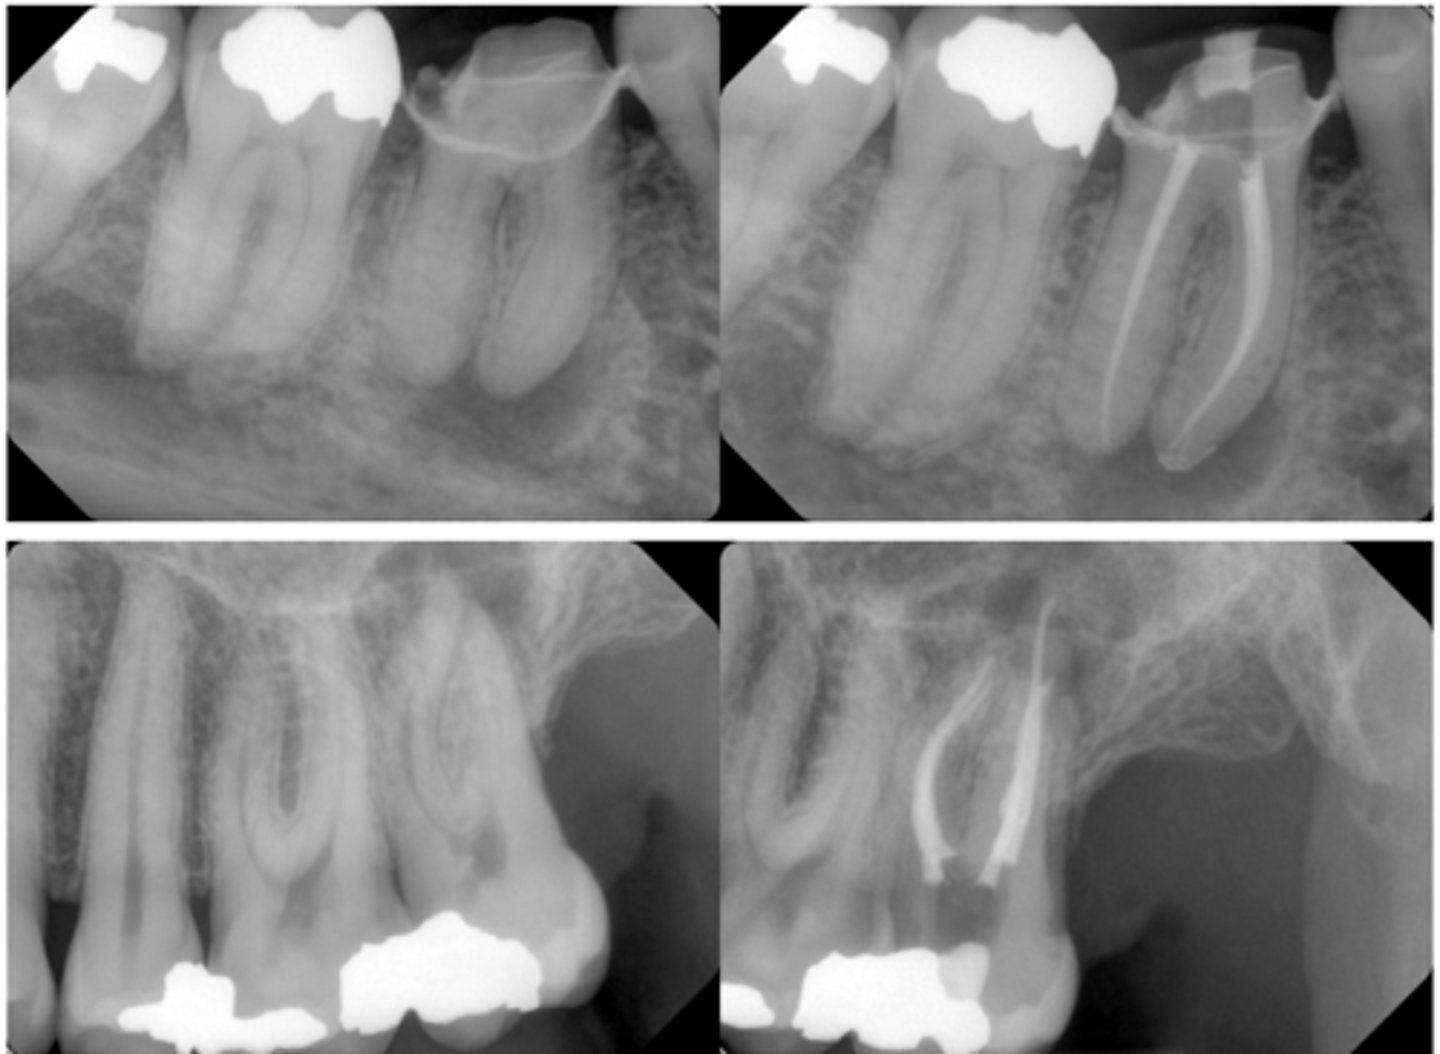

What type of lesion?

Primary endo lesion

T/F: Primary endo lesions may give the impression that they are a primary perio lesion due to deep probing, furcation involvement, etc. however, the only way they are perio is because they pass through the PDL space

true

Primary endo with secondary perio lesions